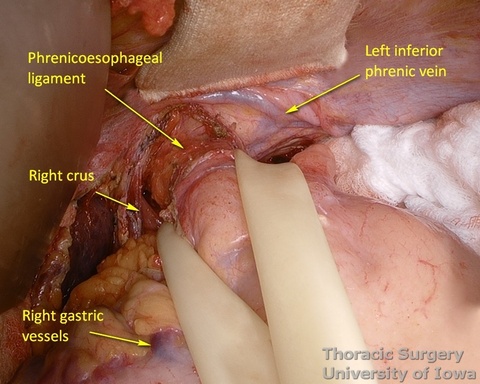

- The phrenoesophageal ligament is divided and the right crus dissected.

- Subhiatal fat ring is exposed after division of the lower leaflet of the phrenoesophageal ligament

- The abdominal esophagus, periesophageal fat, and nodes are dissected and encircled with a Penrose drain for retraction.

- The mediastinum is entered with the combination of sharp and blunt dissection. Note that postradiation adhesions become denser 4-6 weeks after neoadjuvant treatment.

- The transhiatal retractor (See Arshava transhiatal retractor) is positioned in the esophageal hiatus.

- The illuminated transhiatal retractor is advanced into posterior mediastinum under direct vision

- The distal thoracic esophagus is visualized.

- Esophagus is circumferentially mobilized under direct vision using combination of sharp and blunt dissection up to the level of the carina.

- Right lateral esophageal “ligament” (attachments to the parietale pleura, pulmonary ligaments and branches of vagal nerves) is exposed are divided under direct vision

- Left lateral esophageal attachments (“ligament") is divided under direct vision